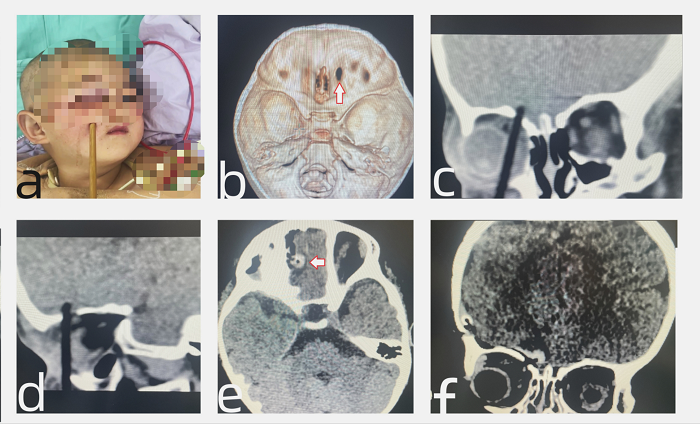

11月15日凌晨,上海儿童医学中心贵州医院儿童神经外科接诊并成功救治了一名不慎将筷子插入头部的2岁患儿。筷子贯穿患儿右侧面部并刺破前颅底插入脑内,儿童神经外科医生接诊后第一时间组织眼科、口腔颌面外科、儿童重症医学科、影像科、麻醉科等多学科力量会诊,迅速为患儿实施手术,成功化解了一场生命危机。

2岁患儿诺诺(化名)在吃饭时不慎摔倒,被筷子刺破右侧面颊,当即哭闹不止,右眼不能睁开,右侧眼睑及眶周肿胀、青紫,诺诺父母立即将孩子送往当地医院。颅脑显示,筷子竟已刺破诺诺的前颅底插入脑内。当地医生建议孩子到上级医院治疗,诺诺一家连夜赶往上海儿童医学中心贵州医院。

手术顺利完成,全程耗时约3个小时。术后患儿转入儿童重症医学科行重症监护和生命支持。1天后,患儿病情平稳,无神经功能缺损,复查CT后顺利转入儿童神经外科普通病房。

术前CT见筷子紧贴右侧眼球刺入脑内,术后CT复查前颅底重建满意